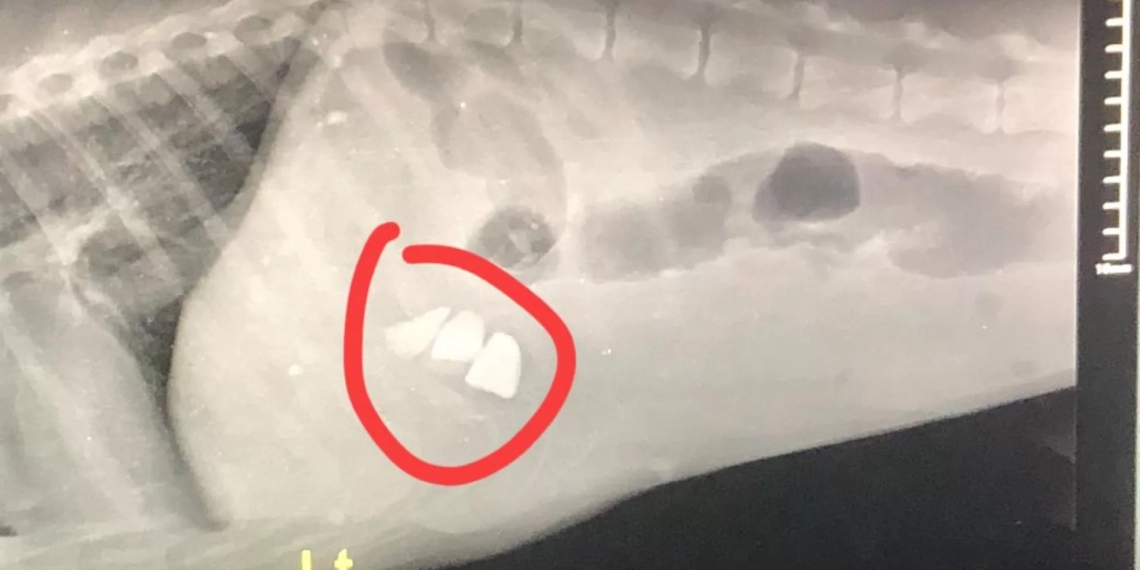

ცხოველთა დამცველი, ტასო ლოსაბერიძე სოციალურ ქსელში რენტგენის ფოტოს აქვეყნებს და წერს, რომ ძაღლმა ქვები იმიტომ შეჭამა, რადგან მას სხვა გამოსავალი არ ჰქონდა და არავინ კვებავდა.

„ამ რენდგენის ფოტოთი გიპასუხებთ ყველას, ვისაც გგონიათ რომ ძაღლები აგრესიულები არიან. ამ წერტილებს ხომ ხედავთ, ეს არის ქვები, რომელიც მშიერმა ძაღლმა შეჭამა, იმიტომ რომ შიოდა და სხვა გზა არ ჰქონდა. აი ასეთი ტანჯვის გადატანა უწევთ ქუჩაში ძაღლებს და თქვენს მოქნეულ წიხლს თუ იგერიებენ, ნუ გიკვირთ.